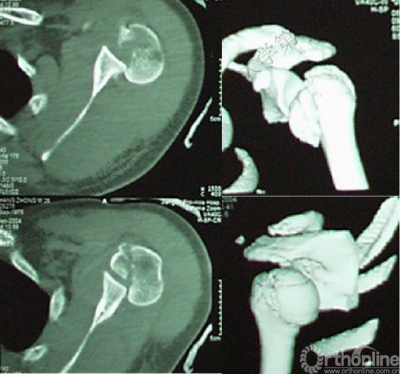

病例3

男性,27岁,车祸致右肩部肿痛、活动受限6小时。

术后肩关节X线片

病例2

VS

Ⅱ型: +肱骨颈骨折+小结节骨折(病例3)。

Ⅲ型: +肱骨颈骨折+小结节骨折+大结节骨折(病例2),以骨折线向肱骨近端外侧壁延伸为另一特征。

五、反Hill-Sachs 损伤对肩关节稳定性的影响